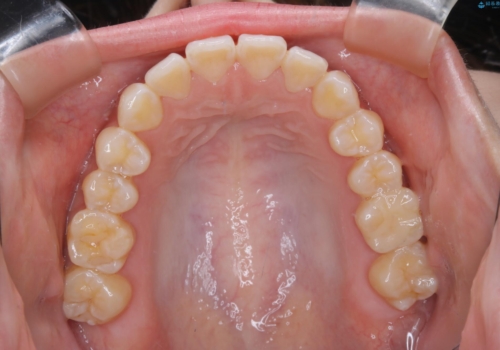

前歯で噛めない:オープンバイト(開咬)を非抜歯インビザラインで治療

オープンバイトの方への治療は、通常抜歯を行いワイヤーによる矯正治療を行うことが多いですが、今回はインビザラインの特性を生かし、非抜歯にて綺麗な歯並びを作ることが出来ました。

舌癖がある方は、歯を内側から押し出す力が日常的に働くため、矯正治療後も歯と歯の隙間が開いてしまうなどの後戻りのリスクが高いことが知られています。舌の正しいポジショニングやお口周りの筋肉のトレーニングを行うことで後戻りのリスクを減らすことが可能です。